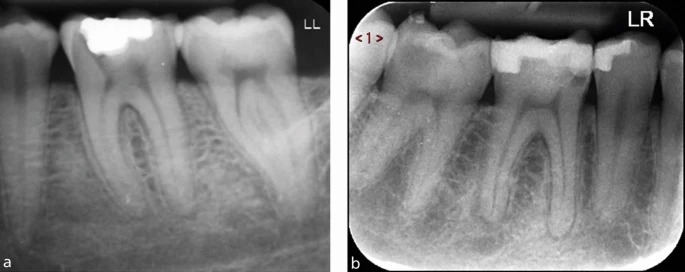

a) Зуб 26, требующий эндодонтического лечения, имеет значительно редуцированную пульповую камеру, что указывает на высокую сложность случая.

b) Зуб 36 также демонстрирует уменьшенный объём пульповой камеры, что повышает уровень сложности. Обратите внимание на гуттаперчевый штифт, показывающий место выхода свищевого хода. Сокращённый размер пульповых камер увеличивает риск ятрогенных повреждений, включая возможность перфорации.

a, b) Прицельные рентгенограммы зубов 36 и 46, оба из которых требуют эндодонтического лечения. В обоих случаях видны крупные, чётко выраженные пульповые камеры, что снижает сложность формирования полости доступа, поскольку камера и устья каналов легко определяются визуально.